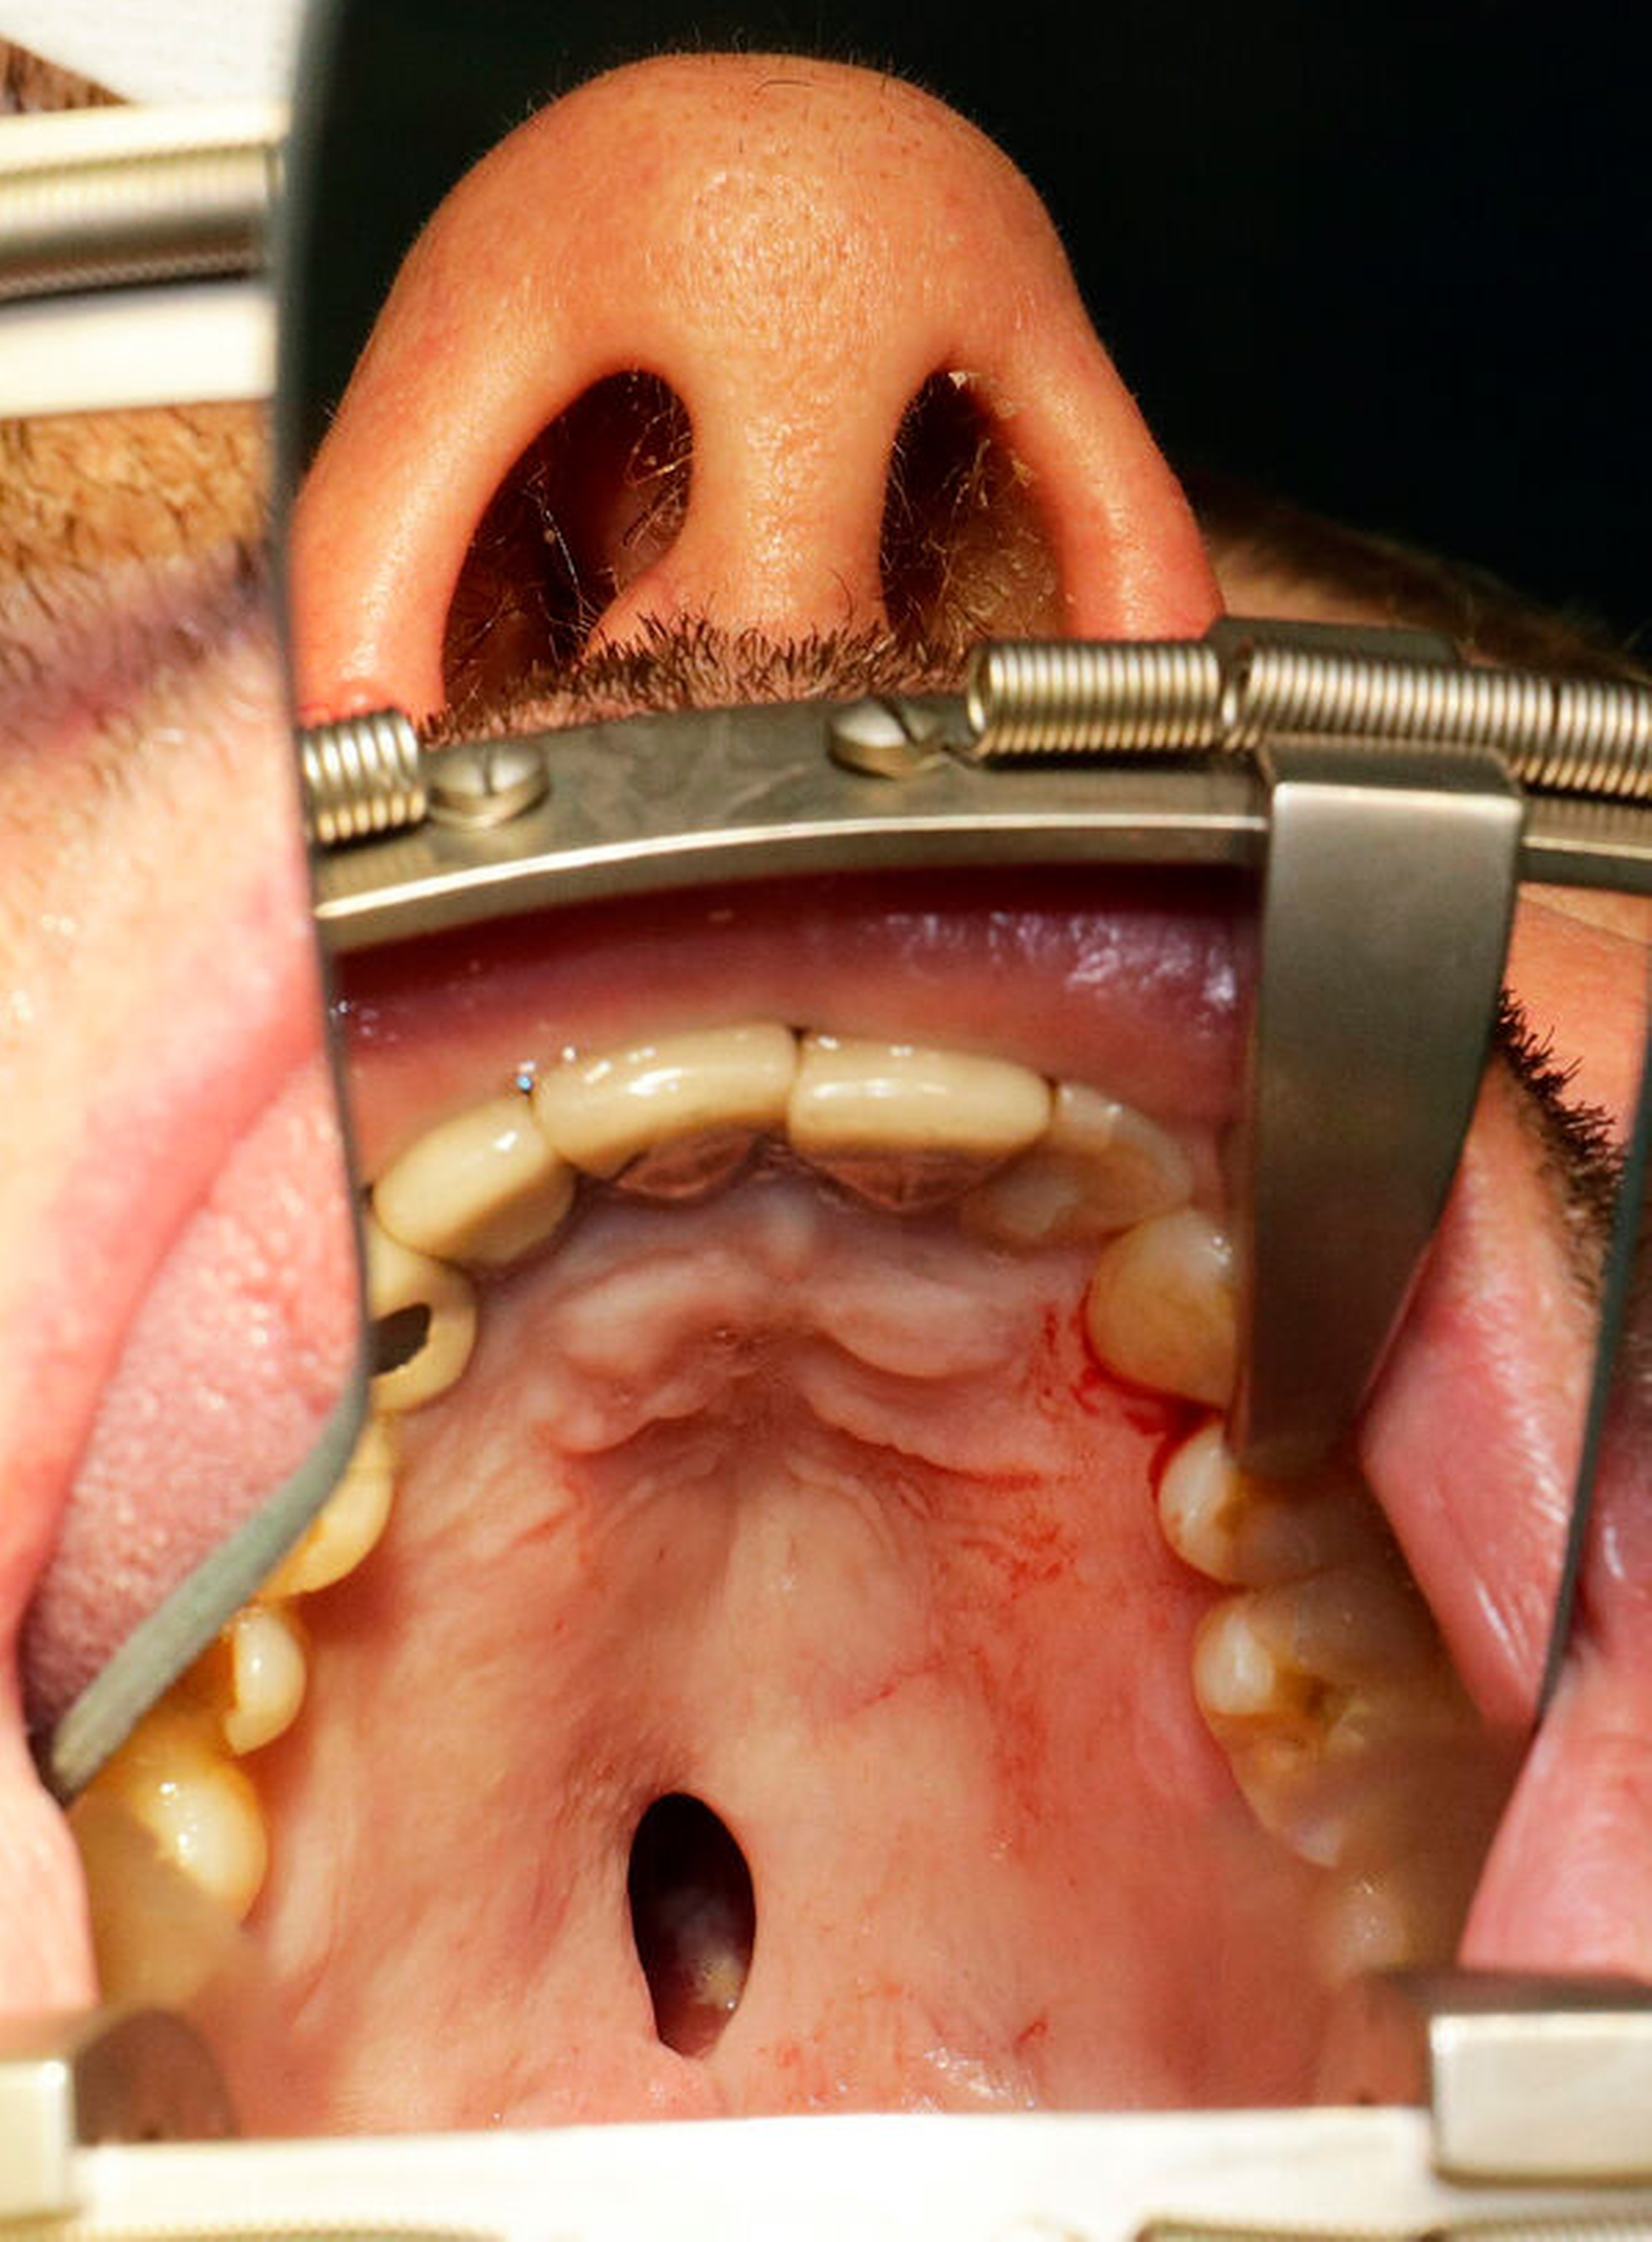

Bei der klinischen Untersuchung zeigte sich ein altersentsprechendes, jedoch sanierungsbedürftiges Gebiss und eine circa 1 cm x 0,5 cm große, glatt begrenzte Perforation im hinteren Drittel des Hartgaumens, ohne Anhalt für frische Blutung. Bei der Nasenspiegelung ließ sich ebenfalls keine frische Blutung feststellen, doch es bestand eine fortgeschrittene Destruktion im Bereich vom Nasenseptum und der Nasenmuscheln beidseits. Die sichtbaren Schleimhäute intranasal waren gerötet, verkrustet und fibrinbelegt. Die regionalen Lymphknoten waren indolent und nicht vergrößert. Differenzialdiagnostisch kamen primär folgende Zustände infrage: sinunasales Karzinom, Schleimhaut- und Drüsen-assoziierte Malignome, extranodales Lymphom, M. Wegener, Lues oder Drogenmissbrauch.

Nach vier Monaten konnten die internistische Therapie unter Remission bei einer deutlichen Besserung des Allgemeinzustands ausgeschlichen und der operative Defektverschluss geplant werden. Die zweischichtige Palatoplastik führten wir in oraler Intubationsnarkose unter stationären Bedingungen durch (Abbildungen 5–7).